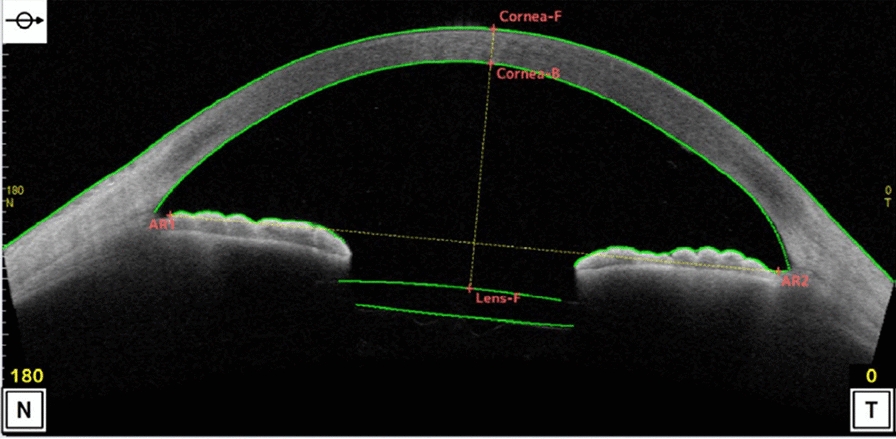

In addition to the ophthalmic examinations, the IOL position was measured using CASIA2 on postoperative day 1, week 1, and month 1. The lens position was measured from the apex of the corneal surface to the center of the IOL (Fig. 2). Subjective postoperative refraction was evaluated by the same technician. Refraction was reported as the spherical equivalent (SE). Due to a possible margin of error caused by different examiners, vision and postoperative IOL positions were measured by the same experienced examiner.

Fig. 2

Measurement of the postoperative IOL position (corneal F to lens F)